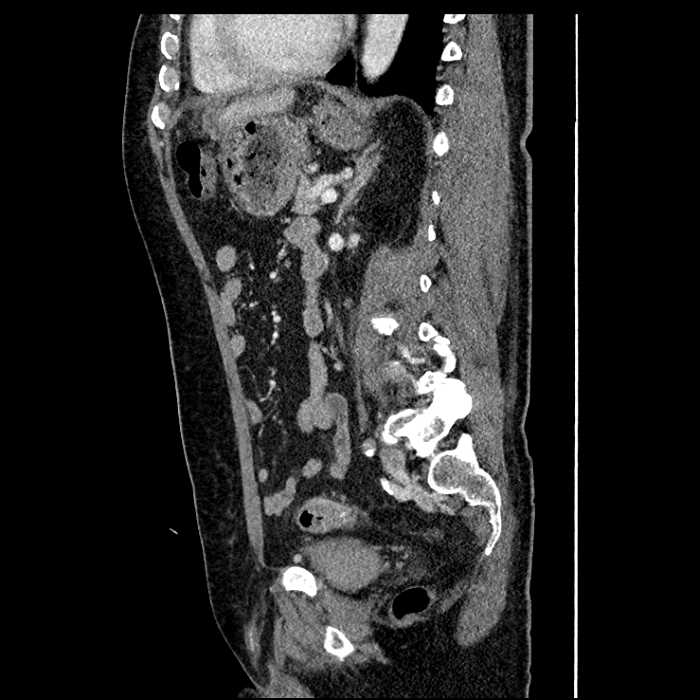

• Large fluid density structure in hepatic segments 7 and 8 measuring 10 x 7 x 7 cm with internal septation and circumferential ill-defined low density compatible with edema

• Peripherally enhancing subcapsular collections along the anterior margin of the left hepatic lobe measuring 3 x 1 cm and 2 x 1 cm

• Mild mural thickening of a segment of the sigmoid colon with adjacent fat stranding and a 1.5 cm fluid and gas collection along the tip of an inflamed diverticulum

• Loss of the normal fat plane between this collection and adjacent loops of small bowel, which demonstrate mural thickening

• High grade stenosis of the left common iliac artery, with the left internal and external iliac arteries remaining patent

Acute sigmoid diverticulitis complicated by a small contained perforation and a large abscess in the right hepatic lobe. Additional small subcapsular abscesses along the anterior margin of the left hepatic lobe.

Additionally, loss of the normal fat plane between the peridiverticular collection and adjacent thickened loops of small bowel raises the potential for an enterocolonic fistula.

High grade stenosis of the left common iliac artery. The left external and internal iliac arteries are patent.

• The classic CT imaging appearance is a double target sign with internal low density surrounded by an internal enhancing rim (capsule) and a low density external rim (edema)

Hepatic abscess showing the double target sign with low density internally surrounded by a thin inner enhancing rim (red arrow) and ill-defined outer low density rim (yellow arrow). Blue arrow indicates an internal septation. Red arrows: additional smaller subcapsular abscesses. Red arrow: focal contained perforation associated with diverticulitis.